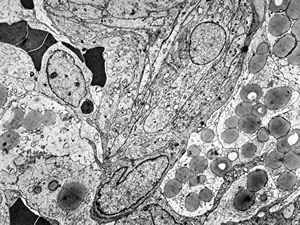

rabbit spinal cord trauma